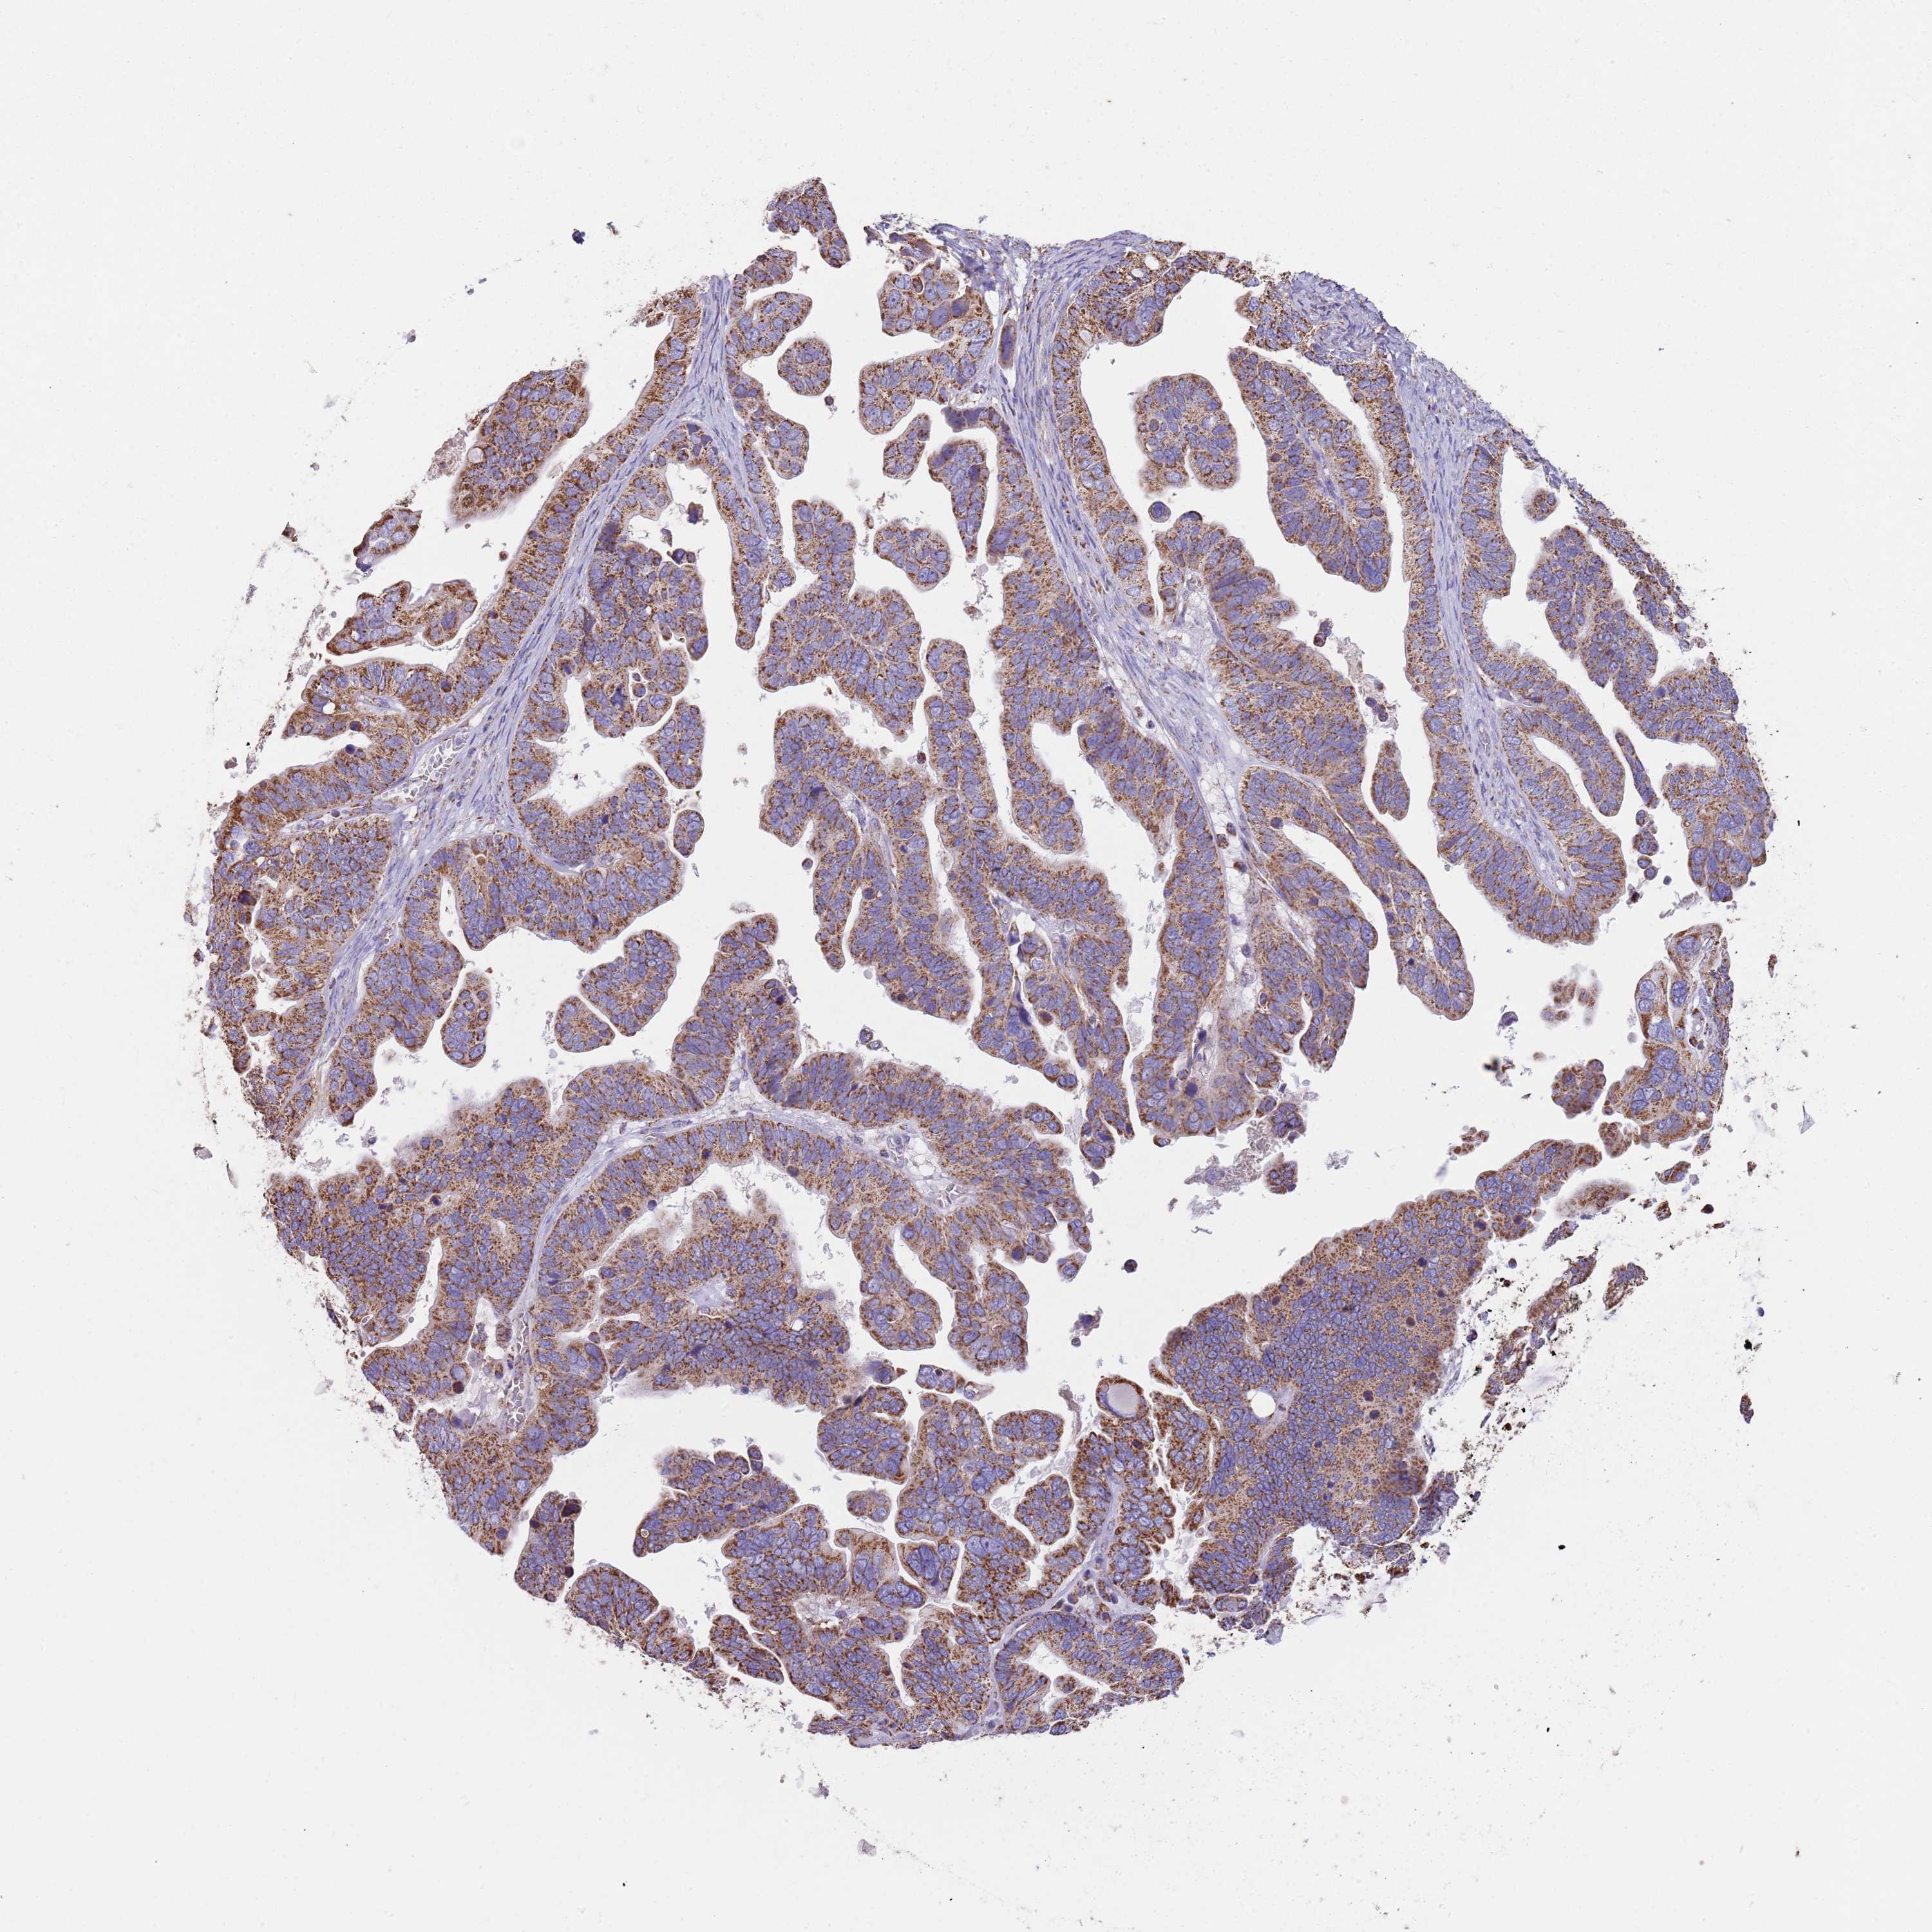

OVARIAN CANCER - Protein expressioni

A mouse-over function shows sample information and annotation data. Click on an image to view it in a full screen mode. Samples can be filtered based on level of antibody staining by selecting one or several of the following categories: high, medium, low and not detected. The assay and annotation is described here.

Note that samples used for immunohistochemistry by the Human Protein Atlas do not correspond to samples in the TCGA dataset.

Antibody stainingi

Antibody staining in the annotated cell types in the current human tissue is reported as not detected, low, medium, or high, based on conventional immunohistochemistry profiling in selected tissues. This score is based on the combination of the staining intensity and fraction of stained cells.

Each image is clickable and will lead to virtual microscopy that enables deeper exploration of all samples and also displays staining intensity scores, fraction scores and subcellular localization as well as patient and tissue information for each sample.

Antibody HPA048392

Cystadenocarcinoma, serous, NOS

Carcinoma, NOS

Cystadenocarcinoma, mucinous, NOS

Carcinoma, endometroid